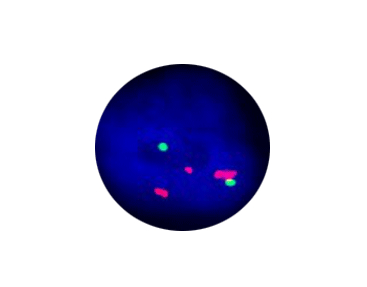

6q21 Segment Amplification

15q22 Segment Amplification

Probe Description: 15q22/6q21